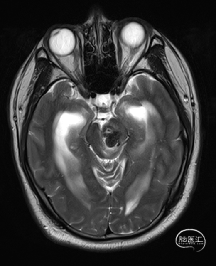

术前MRI检查

术前DTI检查

术前MRI检查提示左侧丘脑中脑海绵状血管瘤并卒中,梗阻性脑积水;

根据MRI及DTI显示,只有在丘脑与上丘之间的点(dot)进入病变才可能在切除病变时最大程度保护神经功能,由于上述原因,该“点”在术中显露极其困难,虽有导航指引,电生理监测的条件下,对术者的耐心、技术、经验及体能依然是极大的挑战;

术前详细的磁共振检查,包括平扫增强,SWI及DTI,可以规划出手术最适宜的路径及切入点;